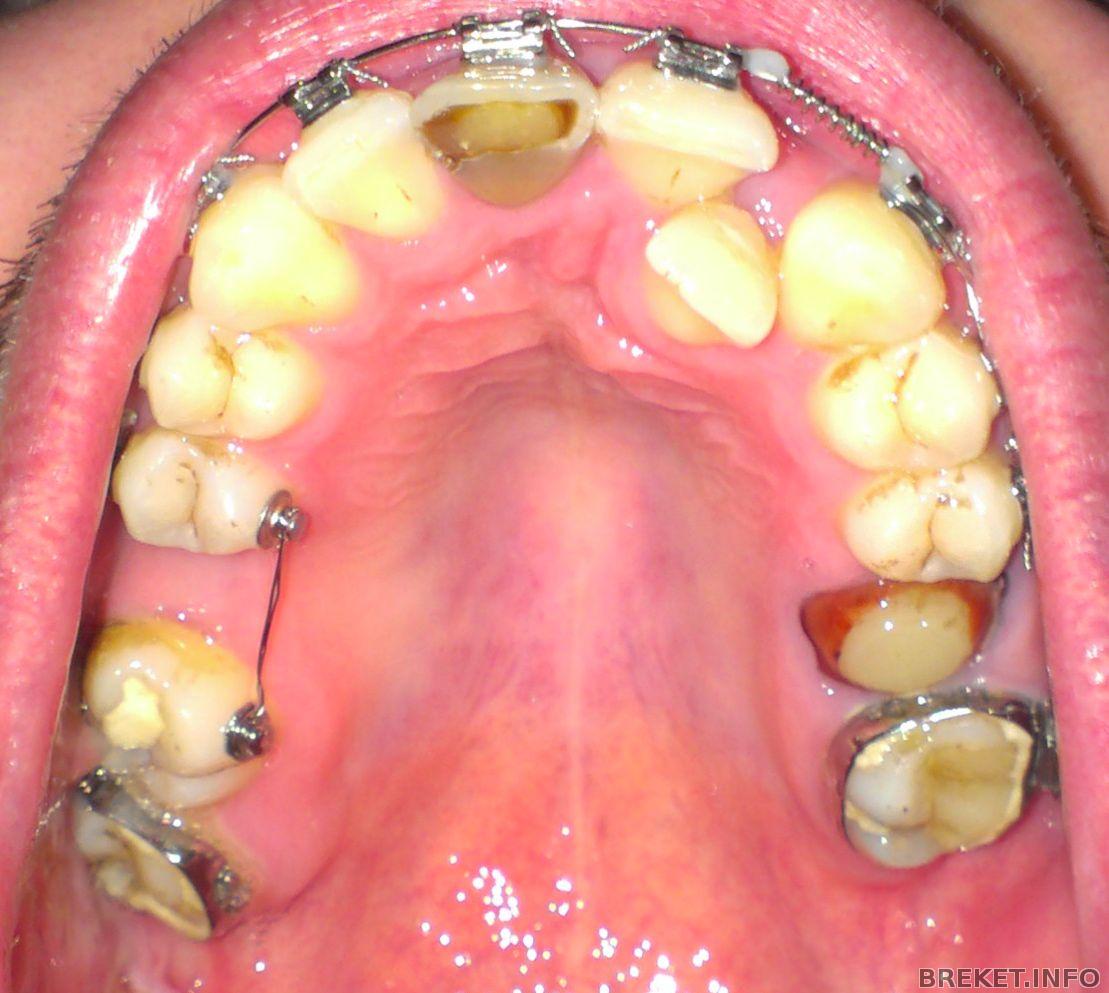

Кстати сегодня был у своей ортофеи на приеме, поменяла она мне проволоку на лигатурные тяги) Поставила как с внешней стороны, так и с внутренней) Днем зуб болел, сейчас чучуть только, когда сильно давишь на зуб... Но хочу сказать что за сегодня моя пятерочка сдвинулась уже на пол 0,5мм наверное) И промежуток единички и троечки еще больше стал!) Не на много, но прогресс есть) Следующий прием 4 февраля, будем дугу менять! Только незнаю на какую...

Хочу сделать чистку зубов, т.к. есть налет небольшой, на фото даже видно, и врач сказал что на ВЧ желательно все фиссуры почистить, и сделать менее выраженными, т.е. не такими глубокими, заполнив их пломбами.. Чтоб они лучше при чистке зубов прочищались) Думаю не плохая идея) Но из-за кнопочек пока нельзя делать чистку, так что как только, так сразу.

В день установки тяги 23.01.14 (вечером).